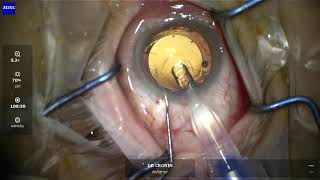

Dr Cronin provides these videos as an educational resource for training ophthalmologists, other ophthalmologists and patients. Dr Cronin specialises in corneal and anterior segment diseases including LASIK, laser eye surgery, cataracts, keratoconus, Fuchs endothelial dystrophy and pterygium surgery.